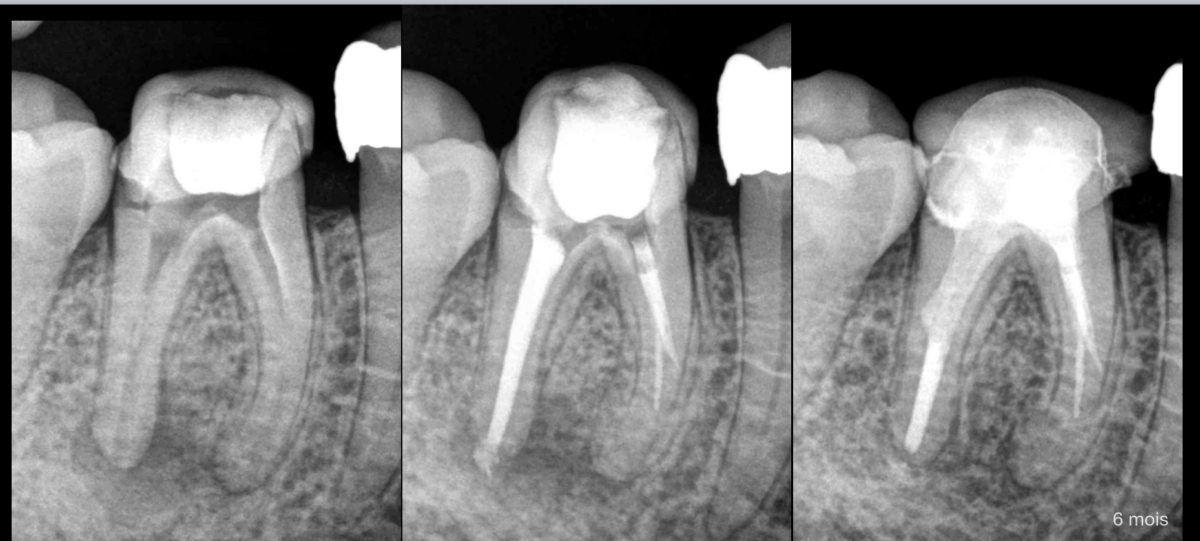

𝐂𝐚𝐬 𝐜𝐥𝐢𝐧𝐢𝐪𝐮𝐞 :

- Patient sans risque médical.

- Traitement déjà initié.

- Parodontite apicale asymptomatique.

🔎 𝐍𝐨𝐭𝐫𝐞 𝐜𝐨𝐫𝐫𝐞𝐬𝐩𝐨𝐧𝐝𝐚𝐧𝐭 𝐧𝐨𝐮𝐬 𝐢𝐧𝐟𝐨𝐫𝐦𝐞 : blocage dans les canaux mésiaux avec des butées et fausses routes présentes dans les racines MV et ML.

➡️ On s’arme de nos meilleures limes, de nos meilleurs ultrasons, et on tente de retrouver la perméabilité canalaire, mais en vain…

📸 𝐒𝐨𝐥𝐮𝐭𝐢𝐨𝐧 𝐚𝐝𝐨𝐩𝐭𝐞́𝐞 : désinfection maximale, obturation et suivi. Le patient est informé et il avait été prévenu de cette éventualité dès la consultation.

⚠️ 𝐒𝐢 𝐥𝐚 𝐜𝐢𝐜𝐚𝐭𝐫𝐢𝐬𝐚𝐭𝐢𝐨𝐧 𝐚𝐩𝐢𝐜𝐚𝐥𝐞 𝐧’𝐞𝐬𝐭 𝐩𝐚𝐬 𝐬𝐚𝐭𝐢𝐬𝐟𝐚𝐢𝐬𝐚𝐧𝐭𝐞, une microchirurgie endodontique sera programmée.